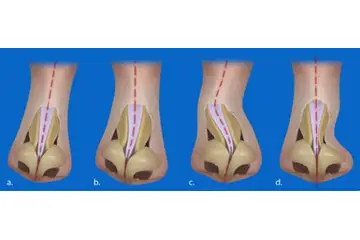

3. Tanı Yöntemleri Diz kıkırdak aşınması tanısı, klinik muayene ve görüntüleme yöntemleri ile konulmaktadır. Bu yöntemler arasında:

4. Tedavi Yöntemleri Diz kıkırdak aşınması tedavisi, hastanın durumuna ve aşınmanın derecesine bağlı olarak değişmektedir. Tedavi yöntemleri şunları içermektedir: